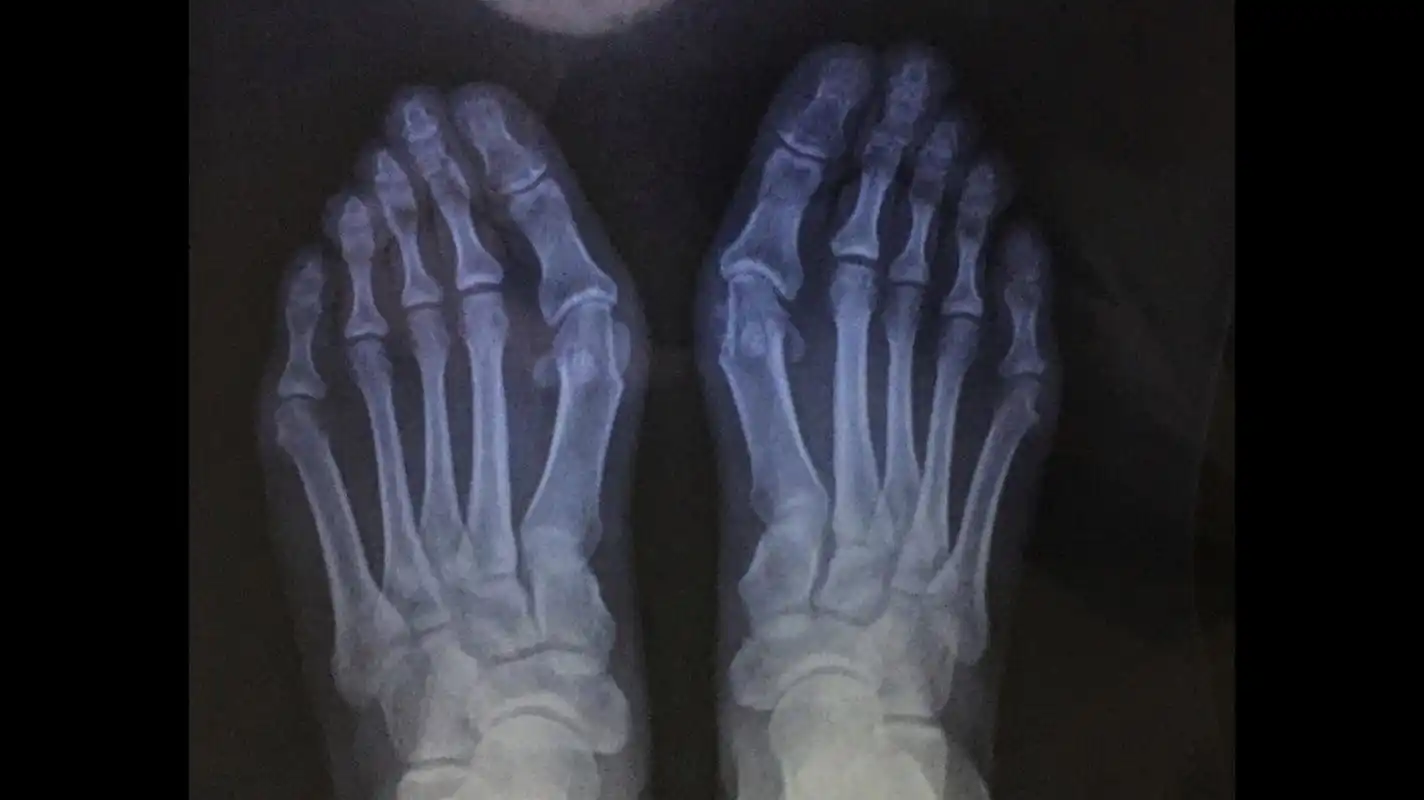

28岁重度拇外翻合并叠趾畸形 #大脚骨 #拇外翻

拇趾向外偏斜,拇趾近节趾骨与第1跖骨成角大于15°,有"大脚骨","大觚

严重拇指外翻形成叠趾畸形脚拇趾外翻可分为轻度,中度及重度外翻畸形.

x光片更直观了解大脚骨 如果单纯去掉凸起能否有效矫正拇外翻呢?